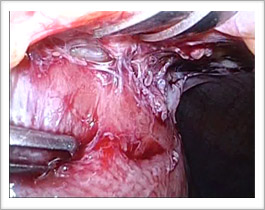

お腹の中の様子です。

腸管がお腹のきずにめり込むように癒着しています。ここを境にして正常な腸管とむくみのある腸管が分かれていました。腸管が自然につり上がるので、観察がしやすいのです。

術前のCTで予想した場所と同じです。